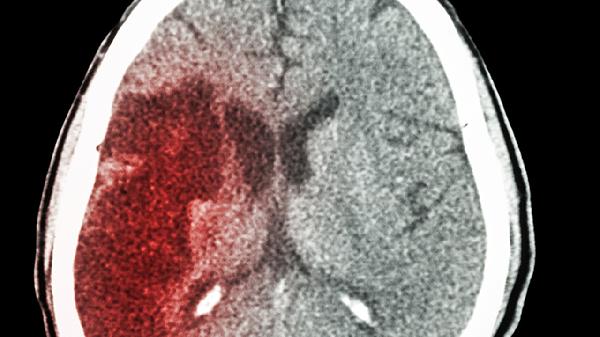

丘脑出血是否手术需根据出血量、患者意识状态及并发症综合评估,多数情况下保守治疗是首选。丘脑位置深且功能重要,手术风险极高,可能损伤周围神经结构导致瘫痪、感觉障碍等严重后果。

当出血量超过30毫升或出现脑疝征兆时,部分医疗机构会考虑立体定向穿刺引流等微创手术。但即使如此,手术清除血肿仍可能破坏丘脑与内囊的连接纤维,导致对侧肢体偏瘫或感觉缺失。术后患者常需长期康复训练,且功能障碍改善有限。高龄或合并心肺疾病的患者更难以耐受全麻手术风险。